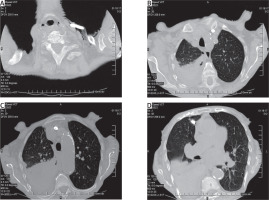

Figure 1

Computed tomography of the chest. Dialysis catheter tip in the right pleural cavity and right-sided pneumothorax with hematoma